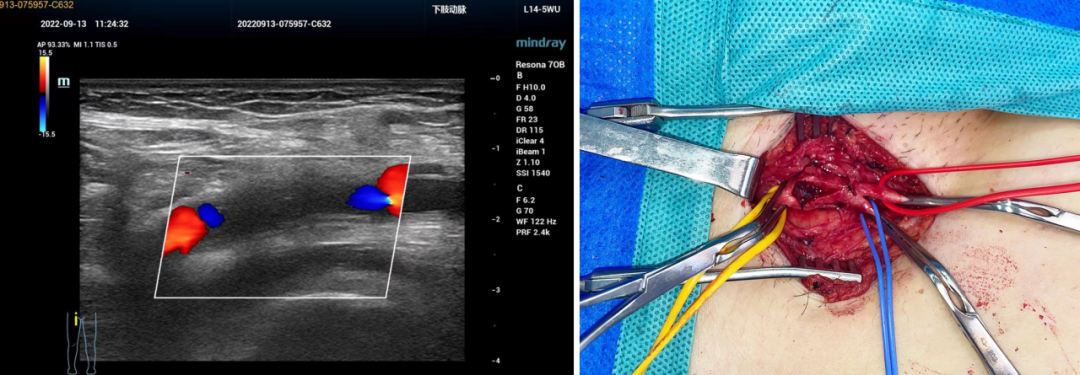

股总动脉穿刺后血栓形成